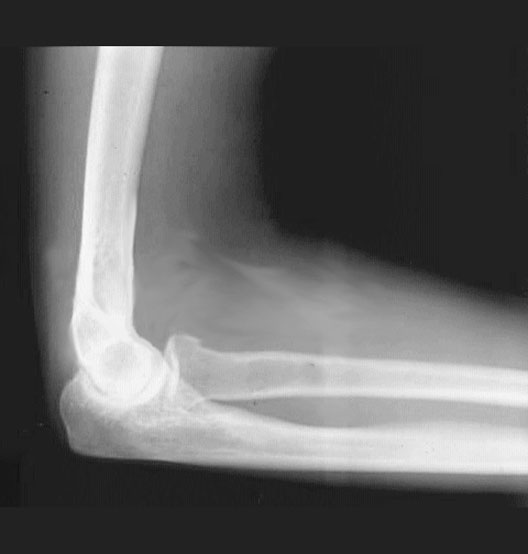

Elbow Flexed

1. Humerus

2. Medial Supracondylar Ridge

3. Coronoid Process of the Ulna

4. Head of the Radius

5. Radius

6. Olecranon Process of the Ulna

7. Ulna